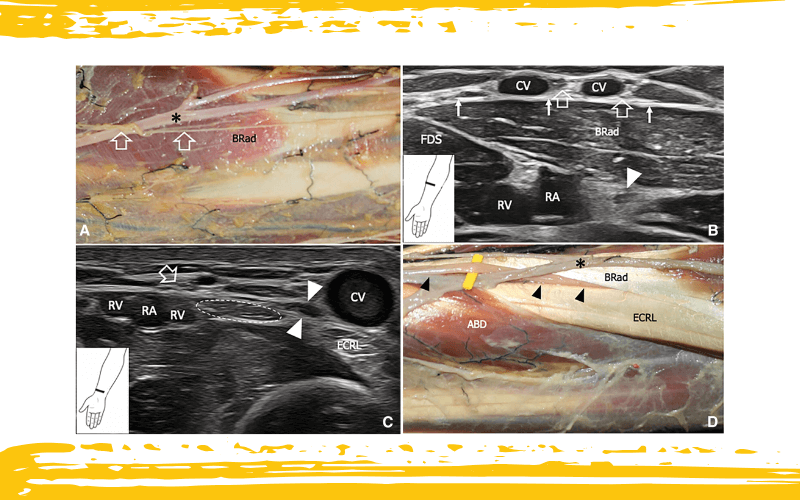

Disección anatómica con correlación ecográfica del nervio cutáneo lateral del antebrazo (LCNF) en el tercio medio y distal del antebrazo.

La imagen A muestra el LCNF (flechas delineadas) en una localización suprafascial, superficial al músculo braquiorradial (BRad) y cruzando ventralmente la vena cefálica (asterisco negro).

En B, la imagen ecográfica obtenida al mismo nivel de la disección anatómica en A, de forma perpendicular al eje longitudinal del antebrazo, muestra las ramas del LCNF (flechas delineadas) entre dos ramos de la vena cefálica (CV), superficial a la fascia profunda (flechas blancas). A este nivel, el LCNF está separado de la rama sensitiva del nervio radial (punta de flecha blanca), la arteria radial (RA) y la vena radial (RV) por el músculo braquiorradial (BRad).

En C, la imagen ecográfica se obtiene distalmente a la intersección entre el abductor largo del pulgar (ABD) y el extensor radial largo del carpo (ECRL). El corte demuestra el LCNF (flecha delineada) y la rama sensitiva del nervio radial (puntas de flecha blancas) superficial a la fascia profunda, ambos a la misma profundidad que la vena cefálica (CV). De hecho, en el tercio distal del antebrazo, la rama sensitiva del nervio radial perfora la fascia entre el ECRL y el tendón del braquiorradial (elipse discontinua) para convertirse en una estructura suprafascial.

Obsérvese la estrecha proximidad anatómica entre el LCNF y la arteria y venas radiales (RA y RV).

En D, la disección anatómica muestra la relación espacial de la rama sensitiva del nervio radial (cabezas de flecha negras), la vena cefálica (asterisco negro), el tendón del braquiorradial (BRad) y el extensor radial largo del carpo (ECRL).

ABD: abductor largo del pulgar; FDS: flexor superficial de los dedos.